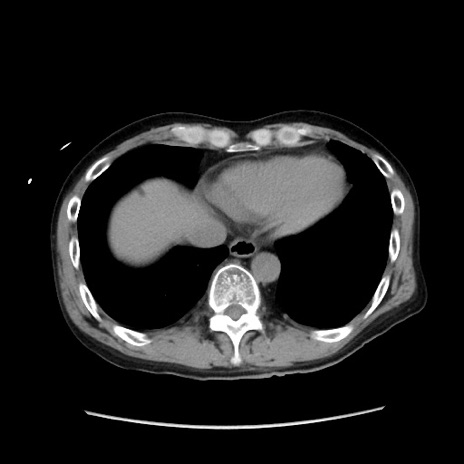

冠状断像